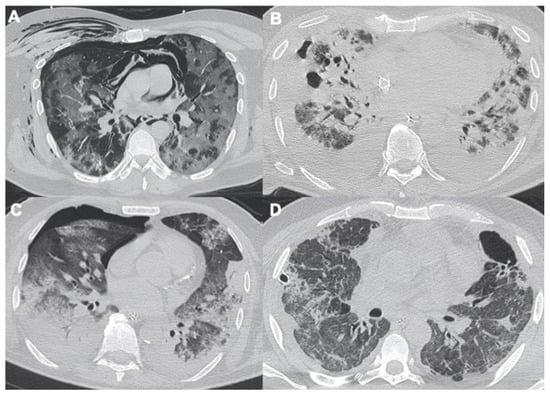

2.2. Acute Respiratory Disease Syndrome

2.3. Pulmonary Embolism